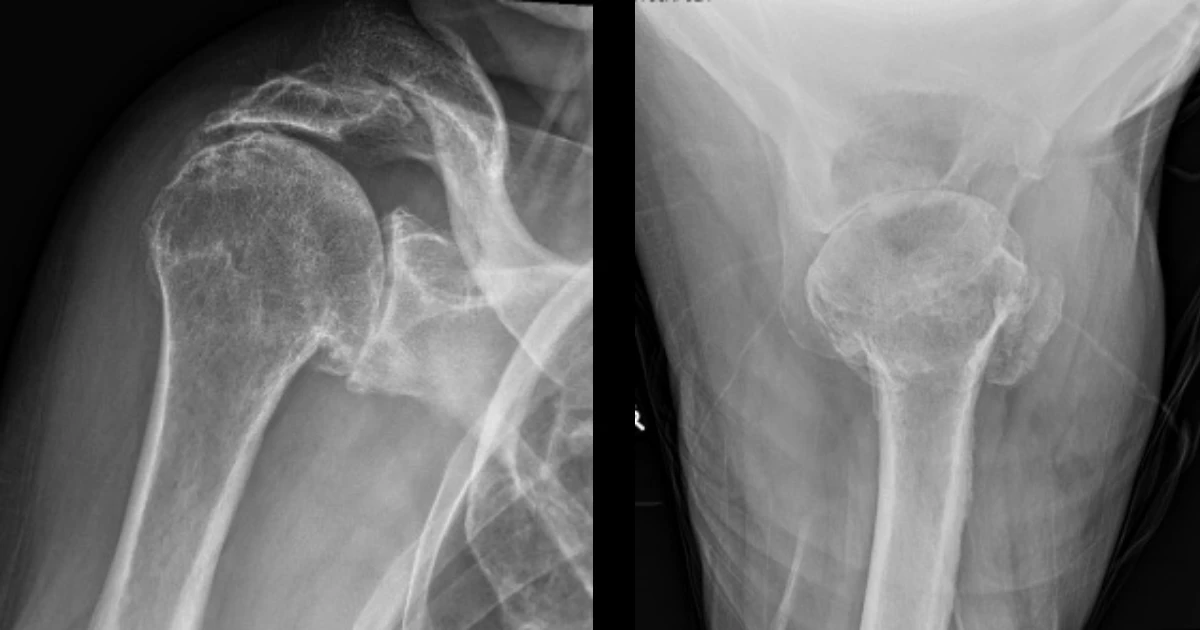

Pre-operative X-rays showing cuff arthropathy of the right shoulder

He returned approximately one year ago with worsening symptoms, most notably pain at night that disturbed his sleep, pain on lifting his arm that limited his ability to perform overhead activities, and pain radiating down his arm. An X-ray at this time confirmed cuff arthropathy of the right shoulder. Given his persistent pain, functional limitation, and radiographic evidence of cuff arthropathy, I recommended CT planning and a right reverse shoulder replacement. He was taking Plavix for cardiovascular prophylaxis, which was reviewed and continued safely in the perioperative period.